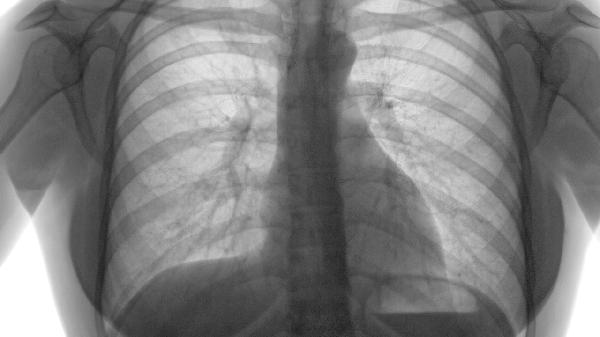

适用于静息状态下血氧饱和度低于88%的重度患者。长期家庭氧疗每日≥15小时可纠正低氧血症,降低肺动脉高压风险。需通过动脉血气分析调整氧流量,目标维持SpO2在90%-93%之间,避免二氧化碳潴留加重。